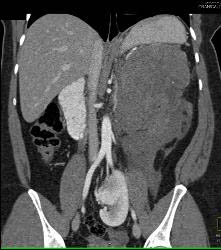

GIST Tumor